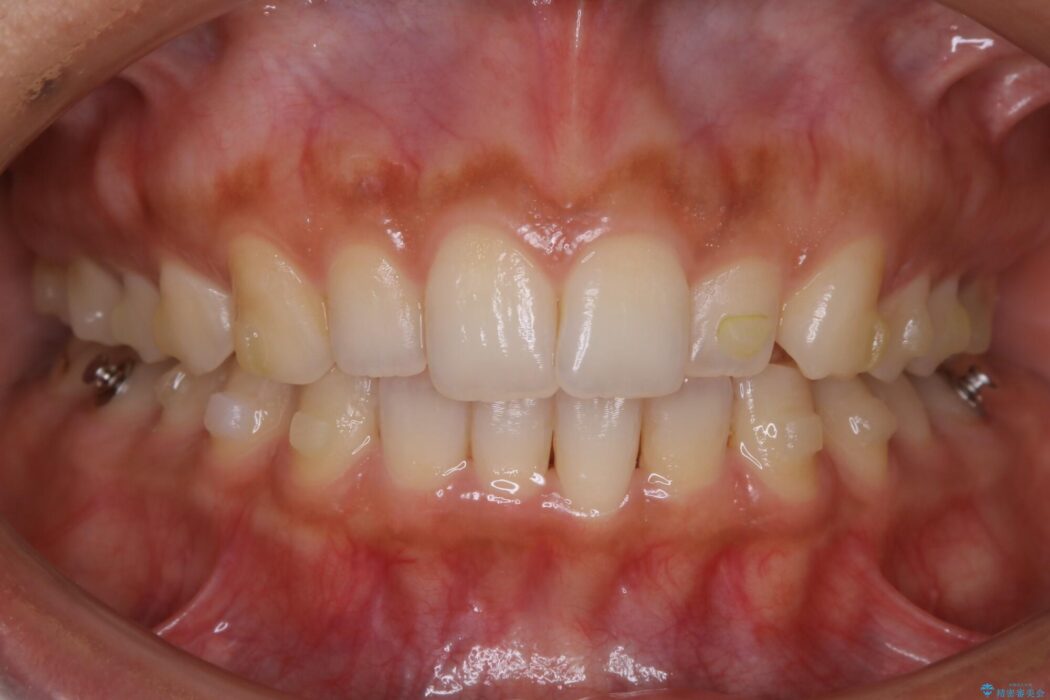

下顎前歯のガタつきを気にされて来院されました。

叢生の度合いにより抜歯は不要と判断しましたので、歯列幅の拡大を主軸に置き矯正治療を行いました。

本症例では下顎の歯列が舌側へ傾くことにより幅が狭まっていましたので、マウスピース治療により歯列弓を拡大しました。